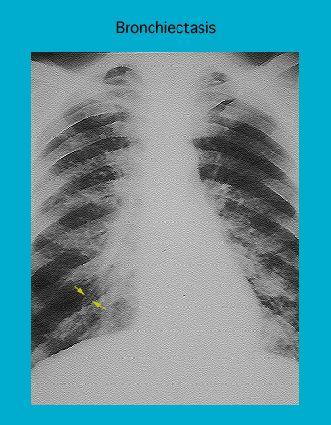

Radiograph showing bronchiectasis